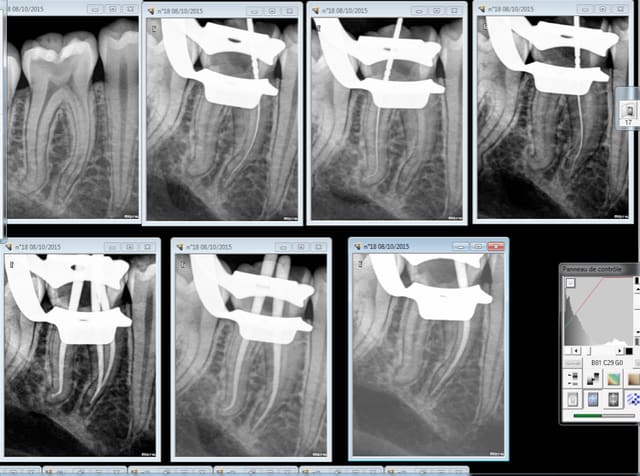

vu la pré op j'avais très peur du résultat mais avec des limes 10 puis 15 avec du glyde et beaucoup de patience, c'est passé! je suis pas mécontent du résultat sur ce truc qui sommeille depuis 40 ans

Endo du matin bonjour ! -)))))

Pulpite à se taper la tete contre les murs sur cette 46. J'ai dépucelé mon quick sleeper 6 fraichement déballé, qui n'a rien à voir avec mon quick sleeper 3 apparemment. -))))

Anesthésie trigone rétro molaire silence opératoire total.

Molaire avec racines ultra longues lt 25 mm partout.

Sx sur entran, largo 3 sur double bague verte pour ouvrir les entrées, s1 sur endomaster, r25 sur wd gold j'usqu'à 18 mm LT.

PUIS cathétérisme lime 10 puis 20 et S1 suivi du R25 à 25 mm. ( finition manuelle au r 25 pour terminer le distal, faut pas tenter le diable ! -))))

Mésiaux sur instrumentés (des fois je ne sais pas m'arrêter quand il faut ! )

Contrairement aux apparences, j'ai mis 45 mn. -))))